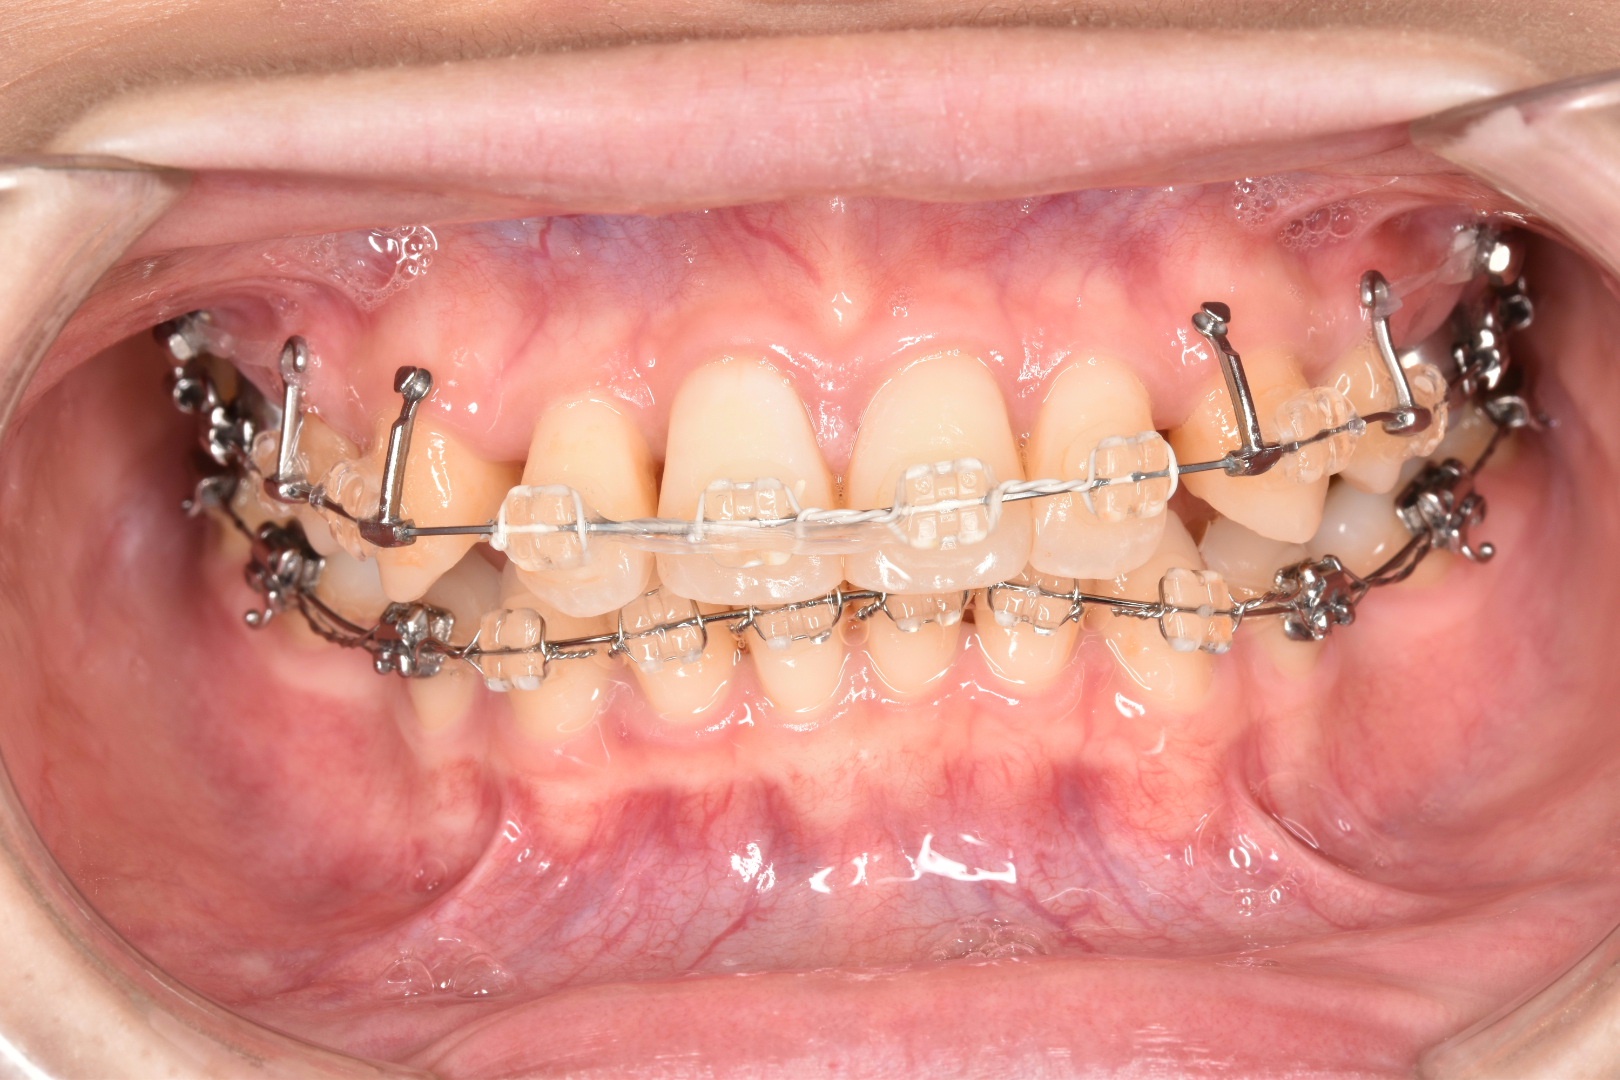

ブラケット装置上下とも外れました〜❤️🧡💛💚💙💜❤️🔥

↓は上のブラケットが外れた物になります。

トータルで3年と2ヶ月かかりました!!!(6月に外しました)

矯正器具外した写真↓